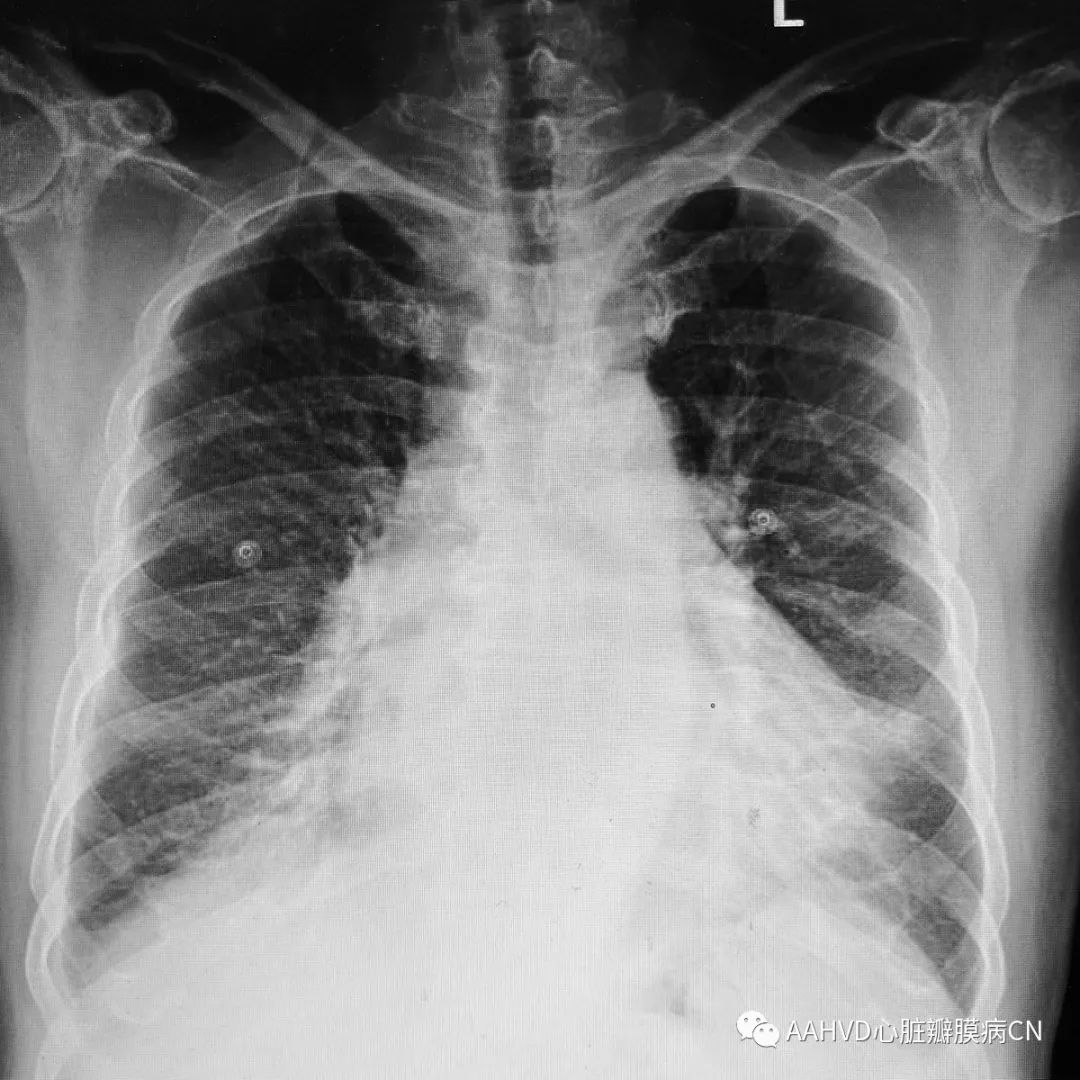

术前胸片

640_2

术前经胸超声:

风湿性心脏病,二尖瓣返流面积9.7cm²(重度返流),瓣口面积1.0cm²(重度狭窄),E前向流速256cm/s;三尖瓣少量返流。